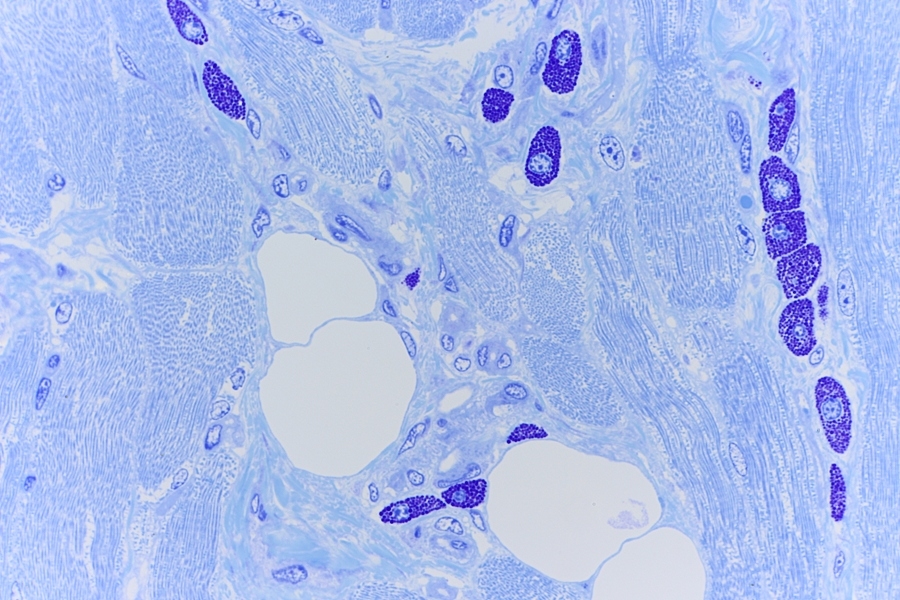

Gegranuleerde mestcellen in tong van een muis.

Mestcellen zijn ovale tot ronde cellen met een doorsnede van 20-30µm, waarvan het cytoplasma rijkelijk gevuld is met basofiele granula. De centrale, ronde kern gaat bij bestudering in een lichtmicroscoop vaak schuil achter de granula. In een coupe vervaardigd uit paraffine zijn de afzonderlijke granulaatkorrels en celkern vaak minder goed zichtbaar. In een coupe van kunststof zoals Technovit of Epon is de coupedikte zo gering dat de mestcel meestal wel met granulaat en kern duidelijk zichtbaar kan worden gemaakt. Zie afbeeldingen op de website (Red).

Mestcellen in een muizen tong preparaat

In de hier getoonde coupes van een muistong zijn geen mestcel ophopingen te zien maar wel zijn de mestcellen in grote hoeveelheden aanwezig. In bijvoorbeeld menselijk weefsel komen veel minder mestcellen voor[Red].

In ‘A practical guide to the histology of the mouse’ is te lezen dat bij knaagdieren deze grote hoeveelheid volledig normaal is en dus geen

ziektebeeld is. Citaat: “Heavily granulated mast cells are commonly seen in normal rodent tongues and can be demonstrated with toluidine blue staining.”[5]